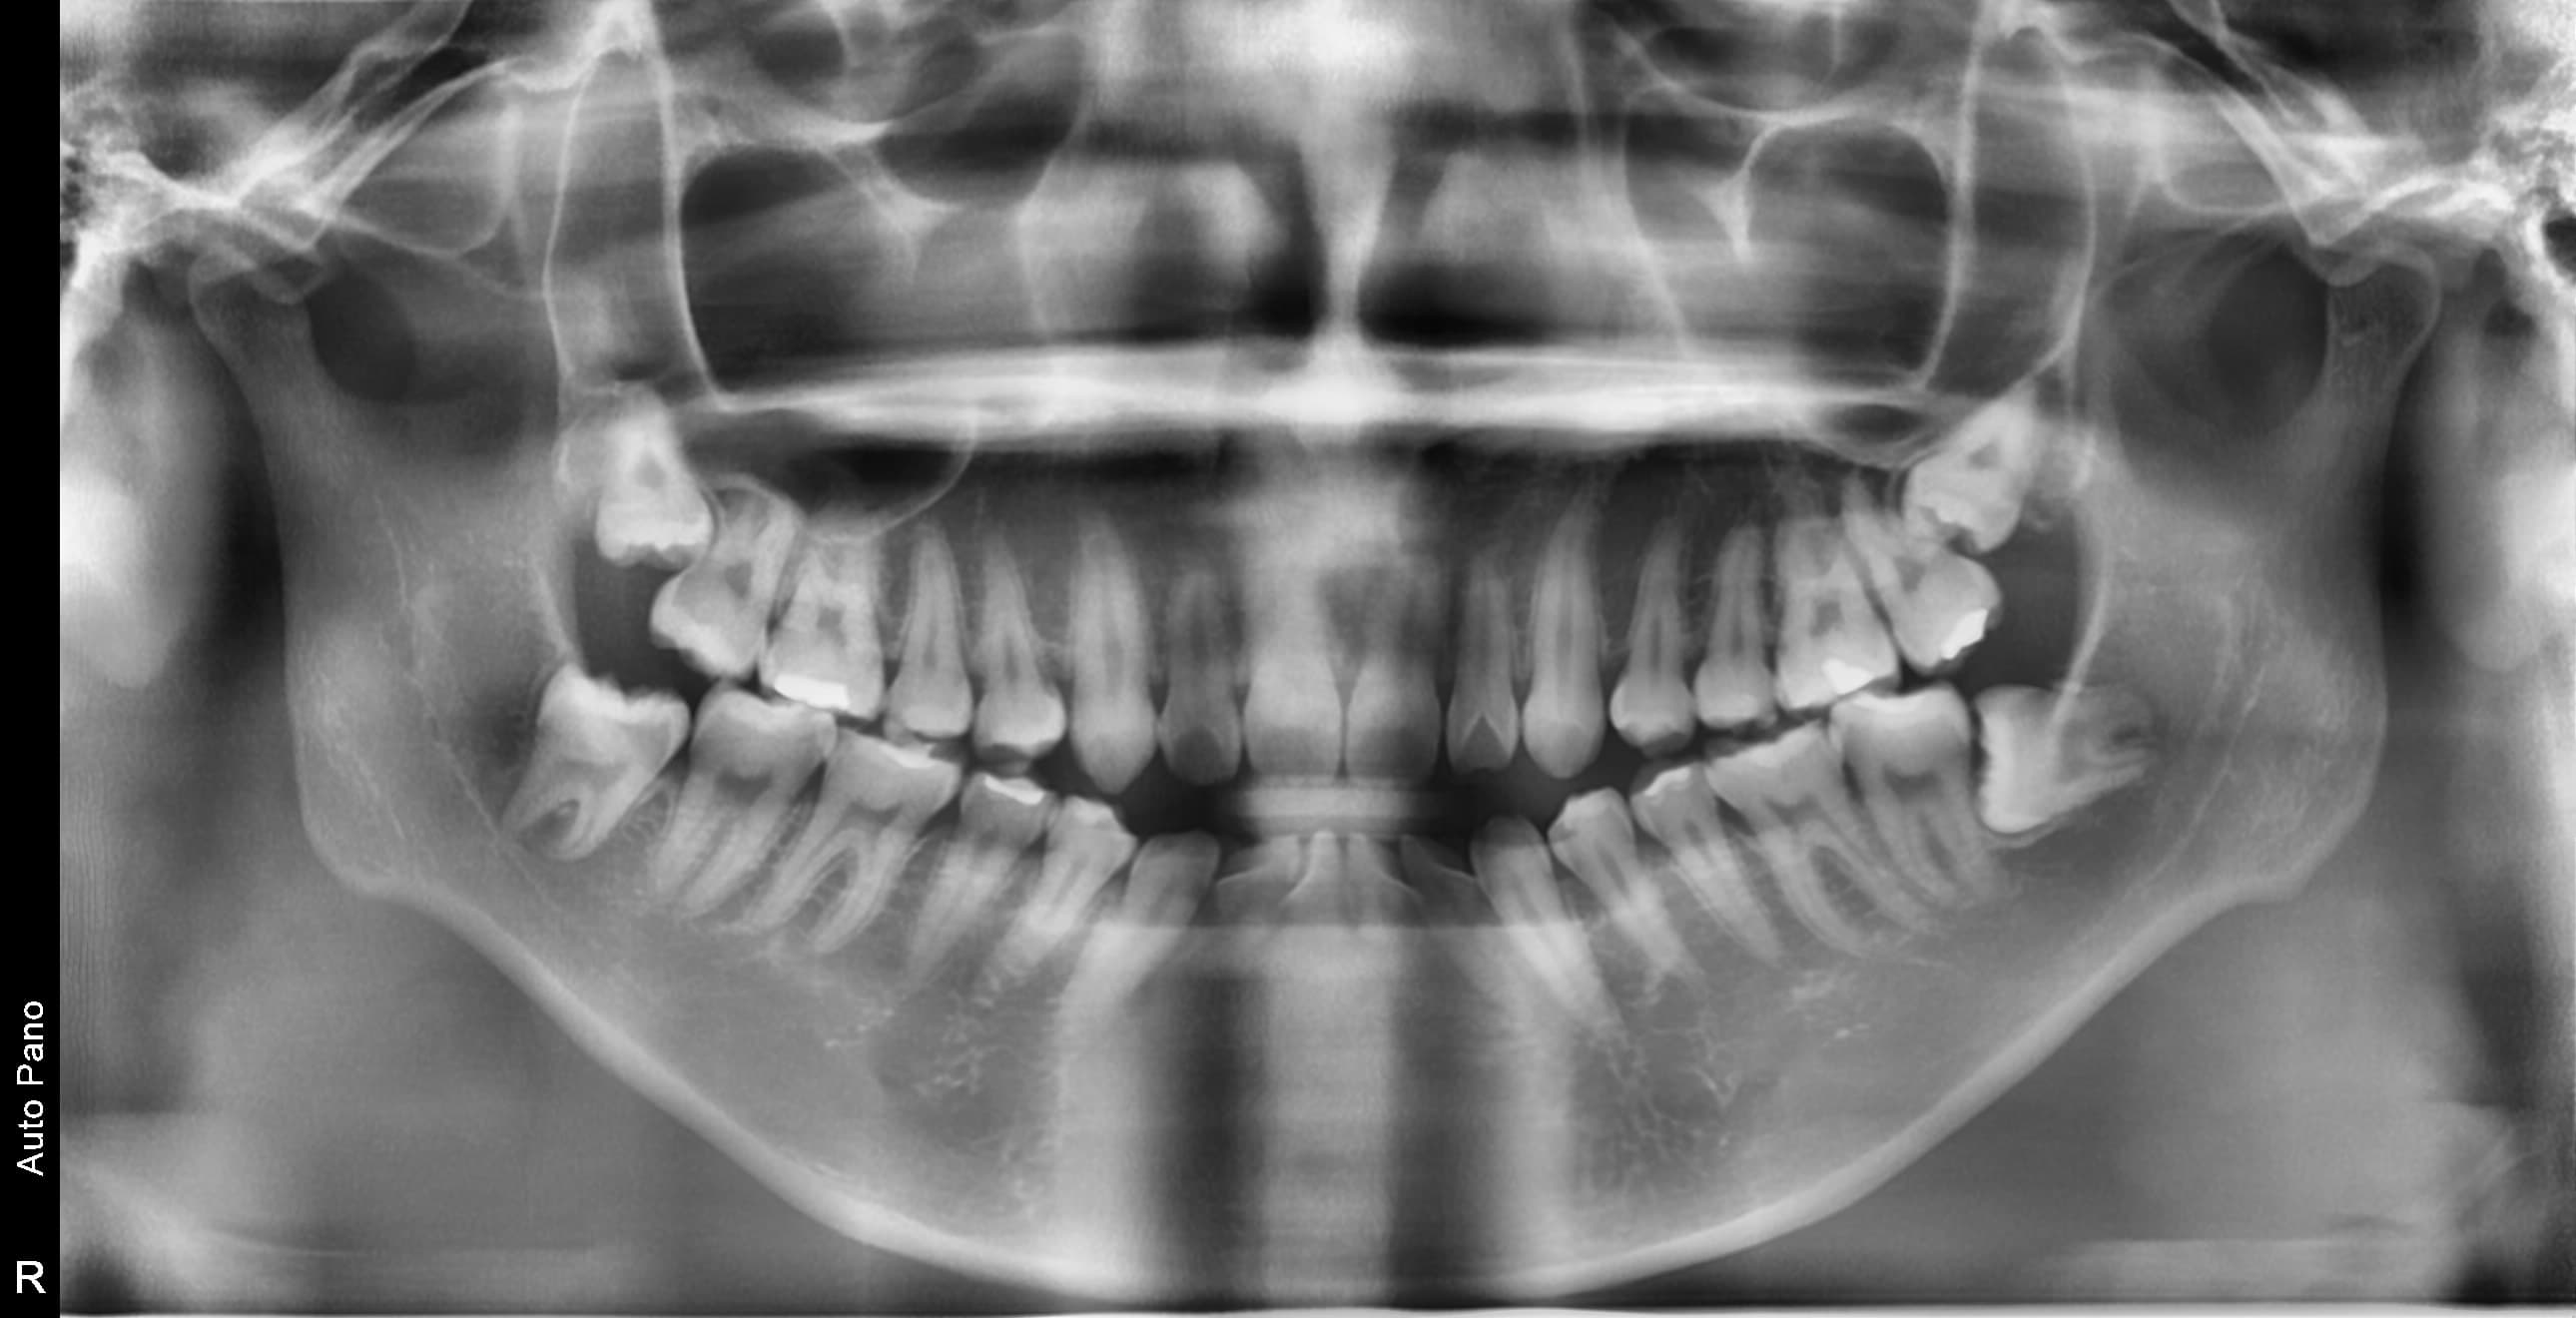

누운 사랑니

옆으로 누워 자라며 옆 치아를 압박할 수 있습니다

염증 발생

방치된 사랑니로 인해 잇몸이 붓고 염증이 생길 수 있습니다